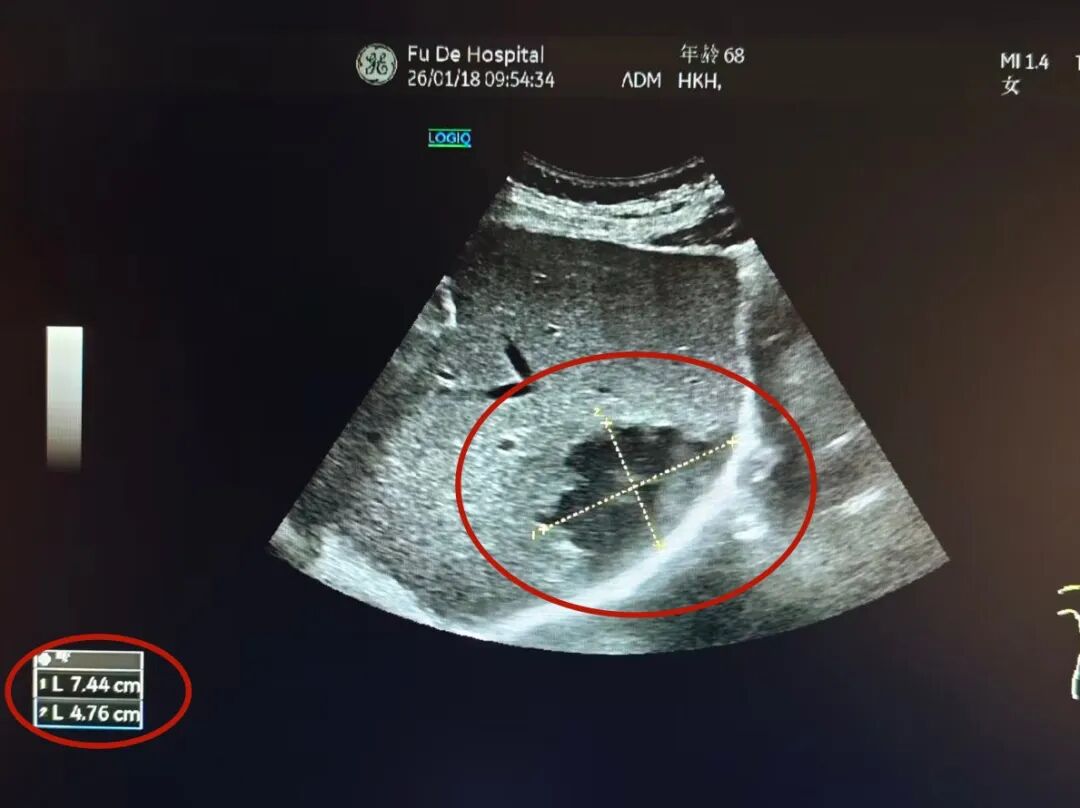

接诊后,通过详细询问病史,结合症状及糖尿病基础,综合内科主任陈星主治医师为其进一步安排肝胆胰脾彩超,结果显示,黄阿姨肝脏内有 一大小近7公分的脓肿, 这正是导致她持续腹痛的“元凶”。